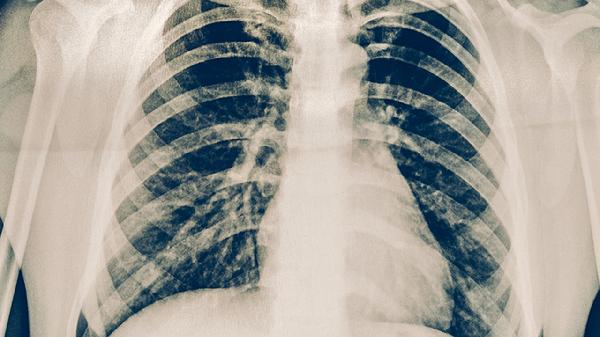

和肺结核一起吃饭有可能传染,但风险取决于多种因素,如患者的传染性、接触距离和时间等。肺结核主要通过空气传播,当患者咳嗽、打喷嚏或说话时,飞沫中的结核杆菌可能被他人吸入。预防措施包括保持距离、佩戴口罩、改善通风等。

1.肺结核的传播途径:肺结核主要通过空气传播。当肺结核患者咳嗽、打喷嚏或说话时,会产生含有结核杆菌的飞沫。这些飞沫在空气中悬浮,可能被周围的人吸入,导致感染。与肺结核患者一起吃饭时,如果患者咳嗽或打喷嚏,飞沫可能污染食物或餐具,增加传染风险。

2.影响传染风险的因素:传染风险取决于患者的传染性、接触距离和时间。活动性肺结核患者的传染性较高,尤其是未经治疗的患者。近距离接触和长时间共处也会增加感染风险。此外,通风不良的环境更容易导致飞沫积聚,提高传染概率。

4.早期发现与治疗:肺结核的早期发现和治疗是控制传播的关键。如果出现持续咳嗽、咳痰、发热、盗汗等症状,应及时就医检查。肺结核的治疗通常需要6个月以上的抗生素治疗,如异烟肼、利福平、吡嗪酰胺等。患者应严格遵医嘱服药,避免中断治疗导致耐药性。